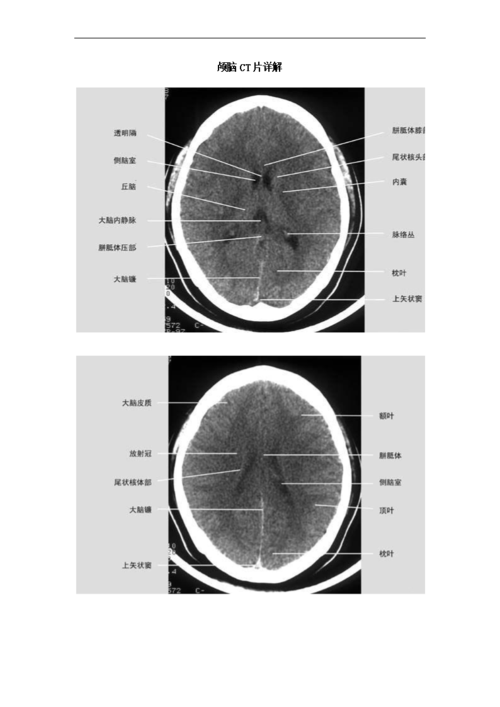

颅脑ct片详解.doc